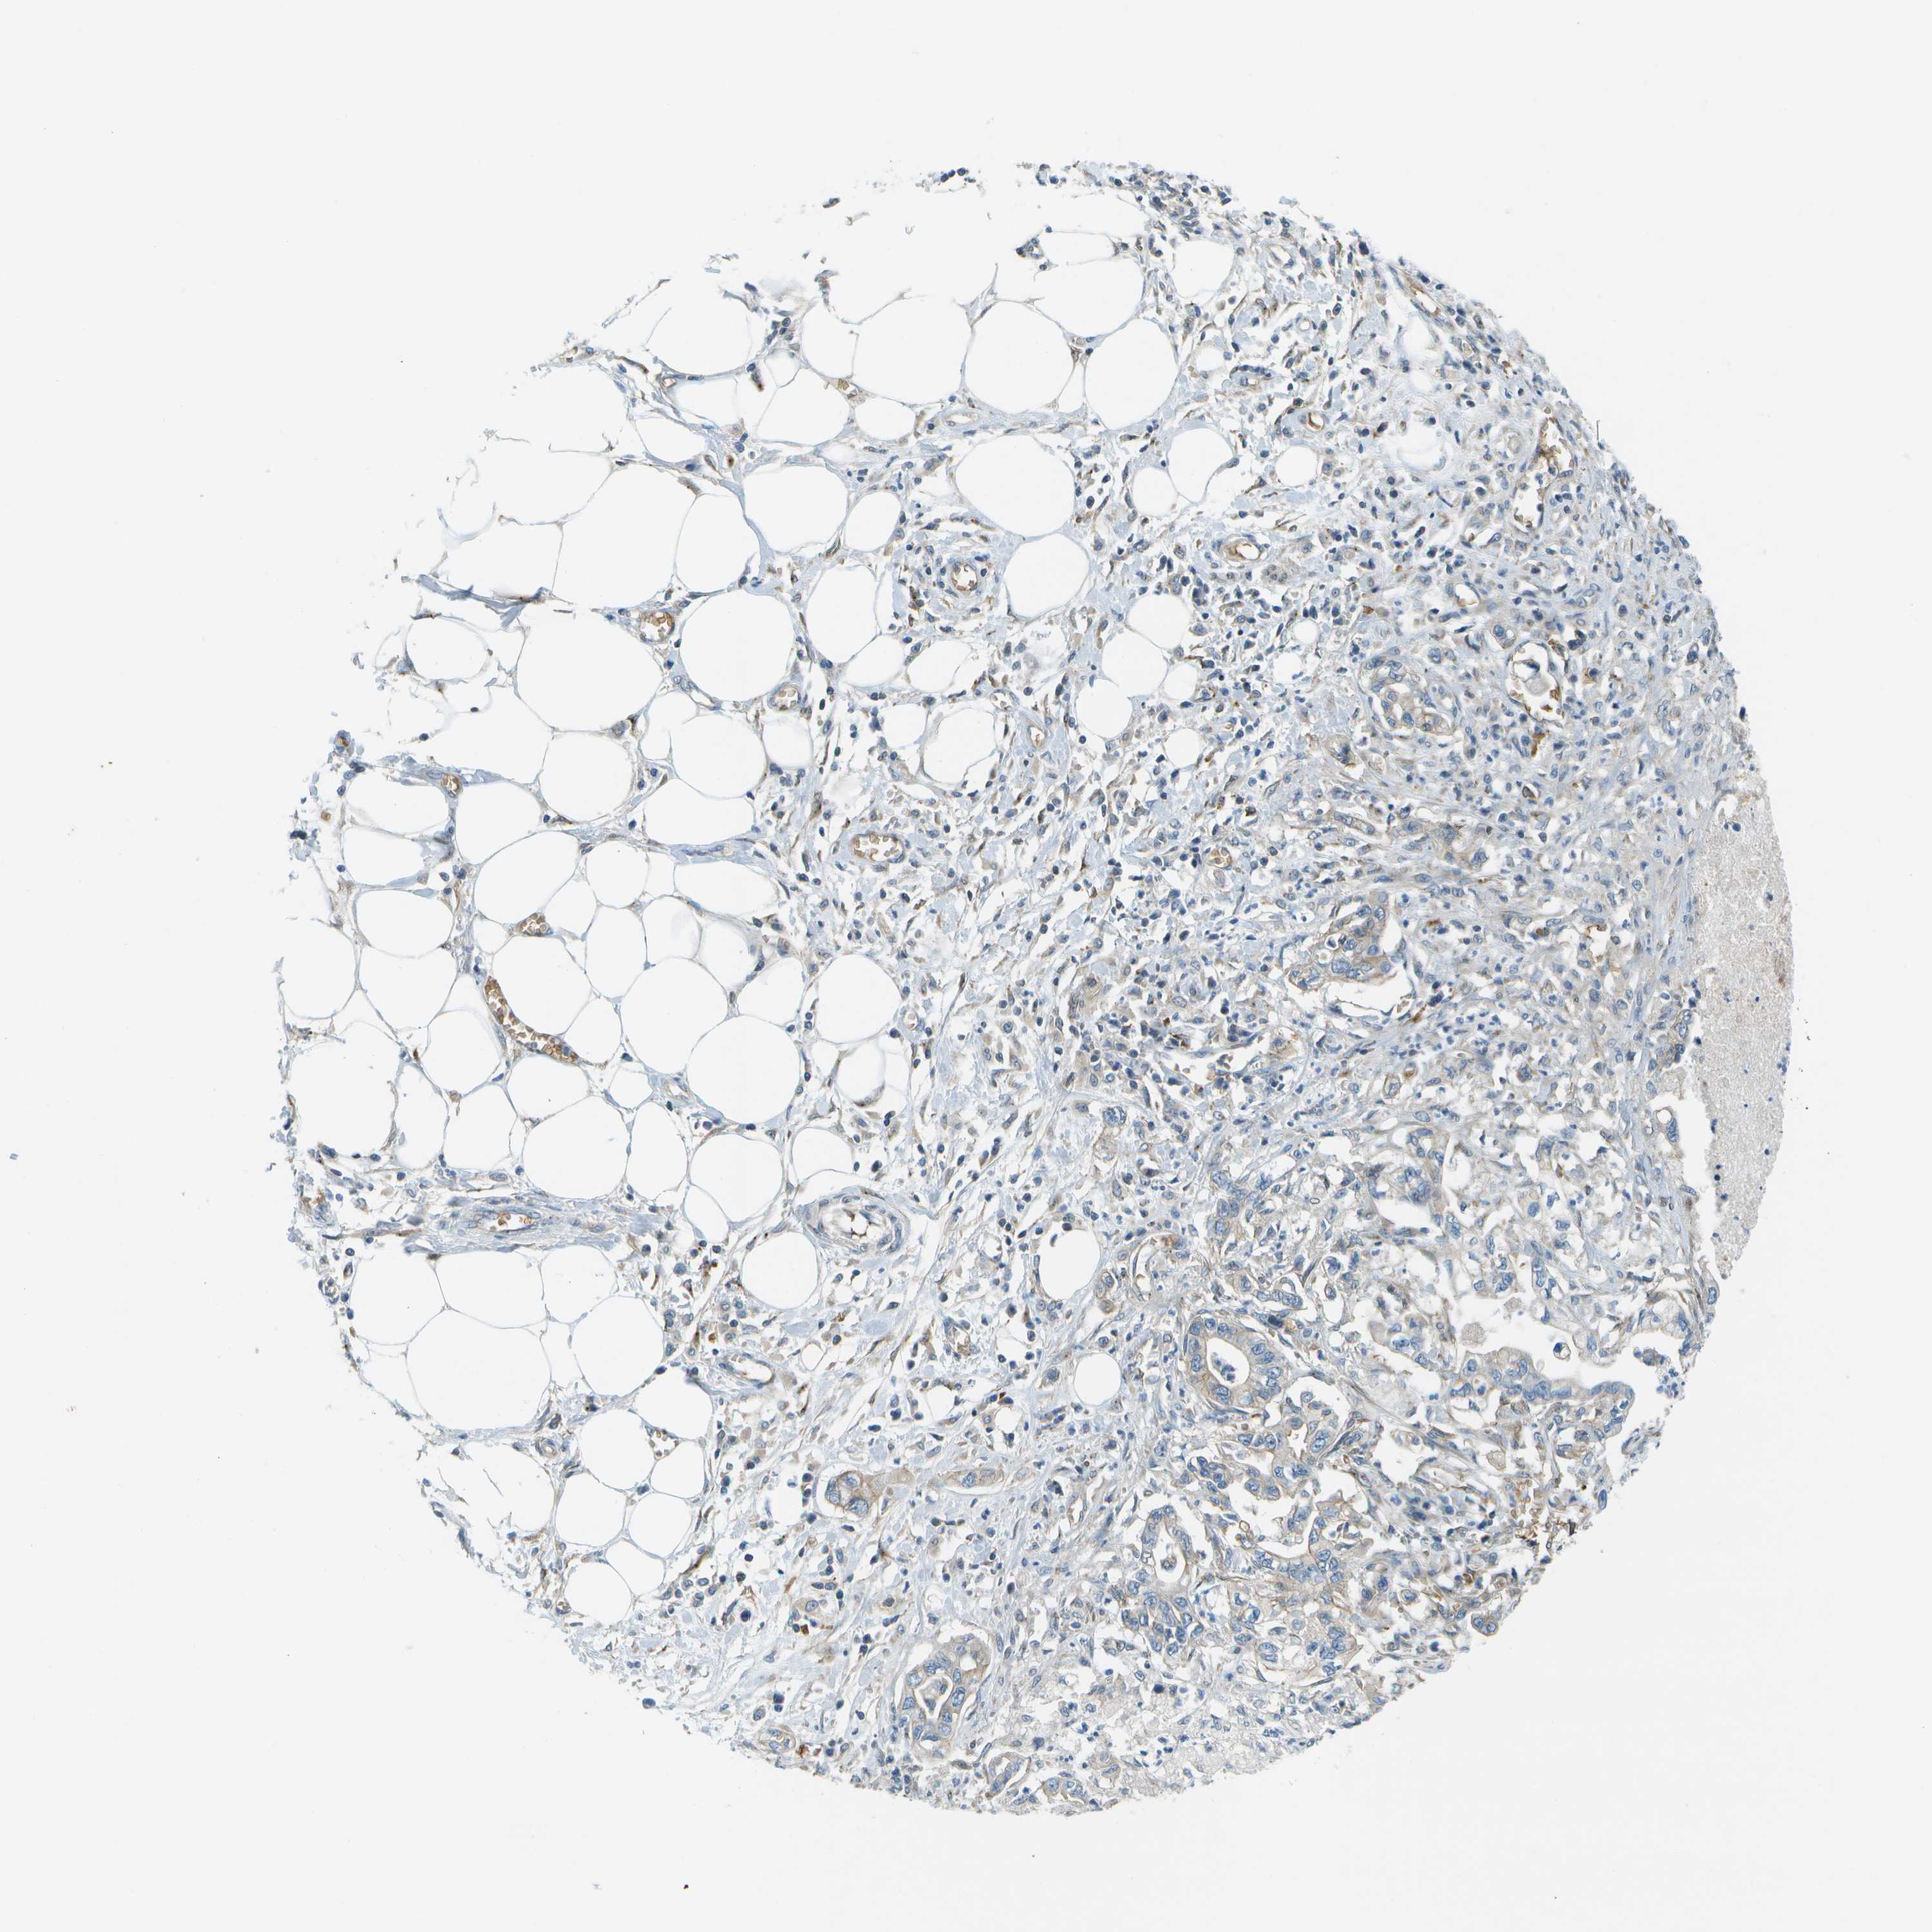

PANCREATIC CANCER - Protein expressioni

A mouse-over function shows sample information and annotation data. Click on an image to view it in a full screen mode. Samples can be filtered based on level of antibody staining by selecting one or several of the following categories: high, medium, low and not detected. The assay and annotation is described here.

Note that samples used for immunohistochemistry by the Human Protein Atlas do not correspond to samples in the TCGA dataset.

Antibody stainingi

Antibody staining in the annotated cell types in the current human tissue is reported as not detected, low, medium, or high, based on conventional immunohistochemistry profiling in selected tissues. This score is based on the combination of the staining intensity and fraction of stained cells.

Each image is clickable and will lead to virtual microscopy that enables deeper exploration of all samples and also displays staining intensity scores, fraction scores and subcellular localization as well as patient and tissue information for each sample.

Antibody HPA016865

Antibody HPA024801

Adenocarcinoma, NOS